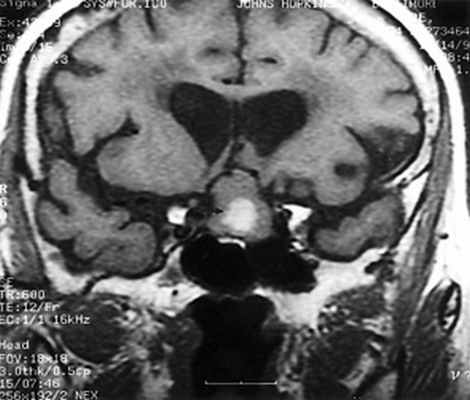

МРТ головного мозга. Т1-взвешенная корональная МРТ. Смешанный ишемический инсульт. Ранняя подострая стадия.

МРТ головного мозга. Корональная Т1-взвешенная МРТ. Апоплексия макроаденомы гипофиза с кровоизлиянием.